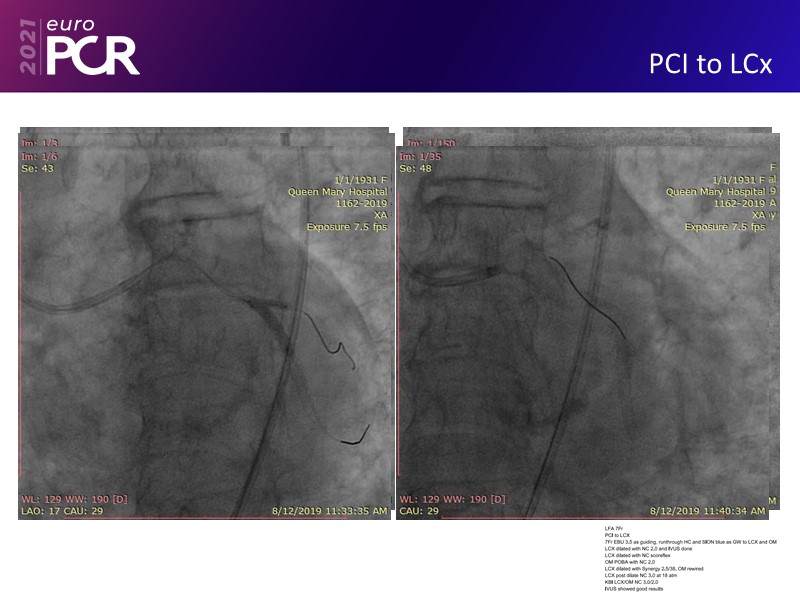

Leave no calcium uncracked--triple vessel disease, severe AS, cardiogenic shock EuroPCR 2021 Clinical Case SPEAKER: J. Fang Previous Next Download presentation